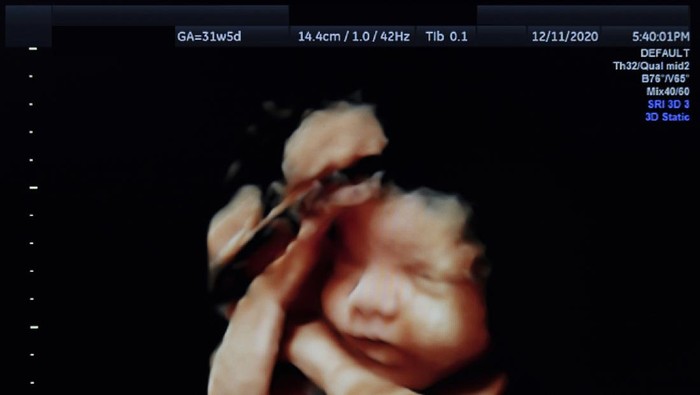

Ultrasonografi 4 dimensi atau USG 4D adalah suatu peralatan radiodiagnostik yang menggunakan bunyi frekuensi tinggi. Mengutip Rumah Sakit Akademik Universitas Gadjah Mada, USG 4D mampu menampilkan gambar dengan kualitas tinggi dengan tampilan 3D yang bergerak layaknya suatu video.

Pemeriksaan ini menggunakan probe 4D konveks frekuensi 1 MHz-5 MHz yang mampu menampilkan organ-organ internal abdomen. Menurut News Medical Life Science, USG 4D memungknkan dokter mempelajari gerakan dari berbagai organ tubuh janin atau bayi.

Pemeriksaan USG 4D dapat menampilkan wajah bayi secara detail, seperti bentuk hidung dan mulutnya. Bahkan, saat bayi tersenyum, menguap, mengisap jempol atau bermain dengan tali pusarnya.